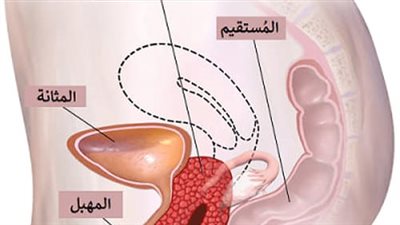

يمكن أن يؤدي أيضًا خلل قاع الحوض، ومشاكل المثانة، ومشاكل الجهاز الهضمي، والحالات المرتبطة بالأعصاب، ومشاكل عضلات جدار البطن إلى آلام الحوض المزمنة.

علاوة على ذلك، يمكن أن يكون ألم الحوض بعد التبول لدى الإناث علامة على حالات كامنة مثل التهابات المسالك البولية (UTIs)، والتهاب المثانة الخلالي (IC)، وبطانة الرحم.

عوامل أخرى مثل حصوات المثانة أو الكلى، ألم الفرج، آلام الفرج المزمنة، خلل في قاع الحوض، والالتهابات المهبلية يمكن أن تساهم أيضًا في الشعور بعدم الراحة.